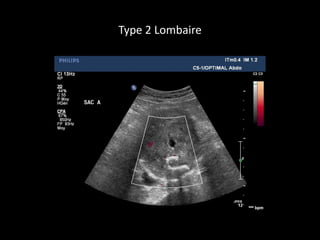

Type 2 Lombaire

ENDOFUITE TYPE 2

TYPE 2TYPE 2

ReperfusionReperfusion parpar

circulation rcirculation réétrogradetrograde

(branche(s) de l(branche(s) de l’’aorteaorte

native)native)

ArtArtèère lombaire,re lombaire,

mméésentsentéérique infrique inféérieure,rieure,

iliaque interneiliaque interne